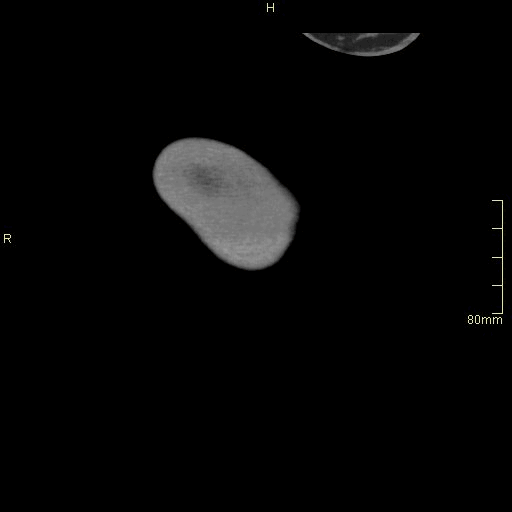

CT Angiography Renal - Maximum Intensity Projection (axial)

CT Angiography Renal - Maximum Intensity Projection (coronal)

CT Angiography Renal - Maximum Intensity Projection (sagittal)

CT Angiography Renal - Subtraction (axial)

CT Angiography Renal - Maximum Intensity Projection 3D VR